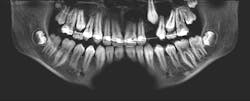

The keratocystic odontogenic tumor of the right posterior mandible was treated in the classical fashion for this entity by aggressive enucleation and curettage. Preoperatively, a 3D stereolithographic model of the mandible was obtained (figures 1-5), with the extent of the lesion defined, primarily to facilitate ease of adaptation should it be determined intraoperatively that a reconstruction plate would be required to reinforce the compromised mandible.

The lesion was removed via an intraoral approach and curetted from the cavity with the cyst intact. A margin of the cavity was removed using a rotary bur, and the cavity was treated with Carnoy’s solution following removal. Tooth no. 31 was noted to be intimately associated with the cyst and was removed. In four months since the surgery, repeat CBCT has demonstrated excellent bone formation within the cavity and no evidence of recurrence (figure 6).